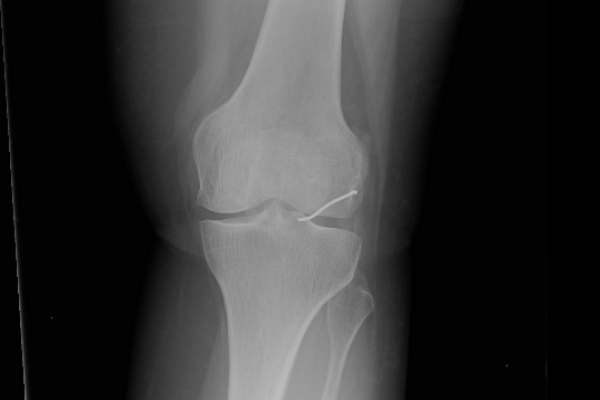

כעבור כשנתיים, ולאחר שספגה מהלומה באזור הברך, החלה האישה לסבול מכאבים עזים ונבדקה על ידי אורתופד. זה שלח אותה לצילומי רנטגן, וגילה, למרבה ההפתעה, כי בברך ישנה פיסת מתכת, והיא זו שככל הנראה גרמה לכאבים. האישה הופנתה לניתוח, שלישי במספר, ובמהלכו הוצא מברכה תיל מתכת באורך 3.5 ס"מ.

ארגון 'הדסה' לא הכחיש את הרשלנות בעצם השארת הגוף המתכתי הזר בגופה של האישה. אך על פי התביעה, השארת התיל המתכתי החריף את הניוון הסחוסי בברכה של האישה, בעוד שמטעם 'הדסה' נטען כי למעשה לא נגרם לאישה כל נזק, למעט כאב וסבל.